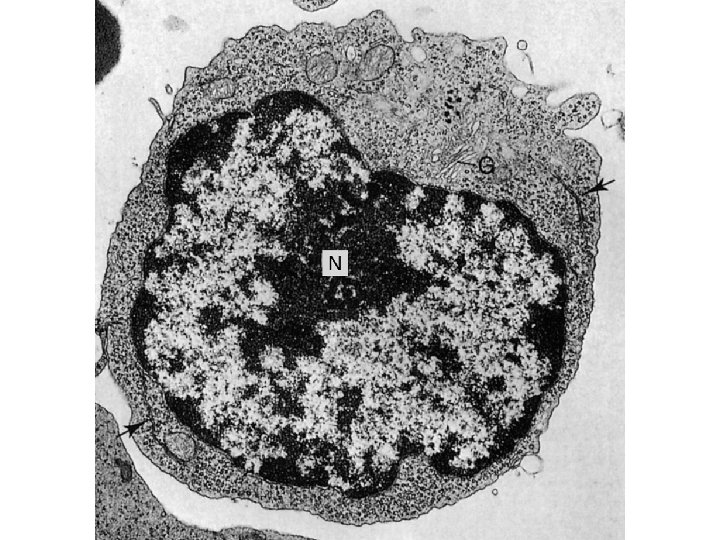

Linfociti – 20 -25% di tutti i globuli bianchi • Aspetto: – Nucleo eccentrico, denso e che occupa circa il 90% della cellula – Citoplasma scarso, color blu tenue con pochi granuli azzurrofili – 8 -10 µm di Ø – Visivamente non si distinguono • Linfociti B (15%) • Linfociti T (80%) • Natural Killer (NK, 5%)